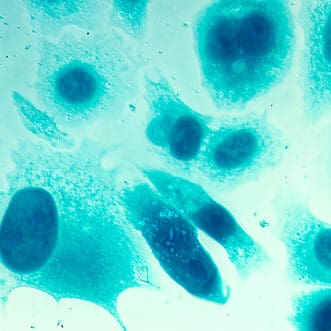

Under local anesthetic, a lubricated ultrasound probe is placed in the rectum allowing the physician to see the shape and size of the prostate—along with any apparent abnormalities or shadows that may indicate cancer. After the prostate gland is injected with numbing anesthetic, slim needles are used to gather samples from several zones of the prostate including suspicious-looking areas (although not all prostate cancers are visible). The collected tissue samples are sent to a pathologist who will examine them to determine if cancer is present.

Grading refers to the way cancer looks under a microscope. When abnormal-looking cancer cells are found, the pathologist ranks them according to the degree of visible change. While early-stage or low-grade cancer cells may look only slightly different from healthy cells, high-grade cancer cells look dramatically different. Each of the tissue samples collected during a biopsy is assigned a number according to the Gleason Grade from 3 to 5 if cancer is present. The number 3 indicates the “least aggressive” grade of prostate cancer, while the number 5 represents the “most aggressive” grade of the disease.